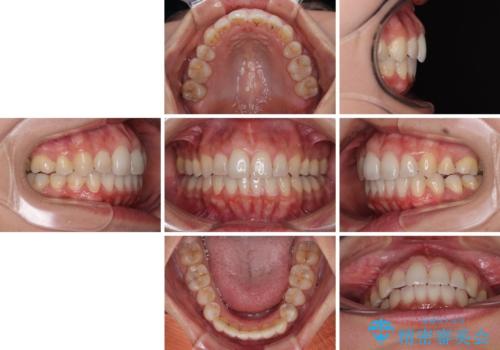

前歯のデコボコを改善 インビザラインの矯正治療

上下顎ともに歯列全体の後方移動とIPR(歯と歯の間を削る)によってデコボコが解消するように設計し、インビザラインにより治療を行うこととしました。

下顎前歯は後戻りを起こしやすいため、舌側を細いワイヤーで固定し、マウスピース型リテーナーで保定を行うこととしました。